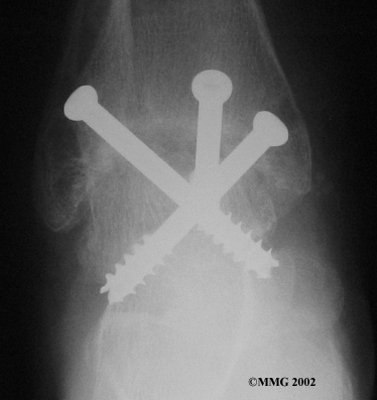

It is important when the surfaces are removed that the angles of the cut surfaces are correct. When the tibia is brought against the talus, the foot should be at a right angle to the lower leg. Once the cuts are made the bones must be held in place while they fuse. This can be done using large metal screws and metal plates if necessary. The screws are usually under the skin and are not removed unless they begin to rub and cause pain.

Inserting the screws

After ankle fusion, the physical therapists at FYZICAL Woodlands North can help you learn to walk smoothly and without a limp. Although time needed for recovery varies among patients, an ankle brace will typically replace your cast after eight to 12 weeks. Your surgeon will take X-rays frequently to see if the bones are fusing together. You will probably need to use crutches during the time you wear the cast. As the fusion grows stronger, you will begin to put more weight on your foot when walking.